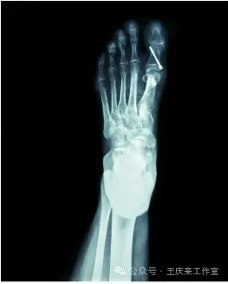

手术治疗:对于中重度拇外翻或保守治疗无效者,可能需要通过手术纠正拇趾位置。手术方式有许多种,主要目的是切除增生的骨赘,重建相关韧带结构,以恢复正常步态和缓解疼痛。